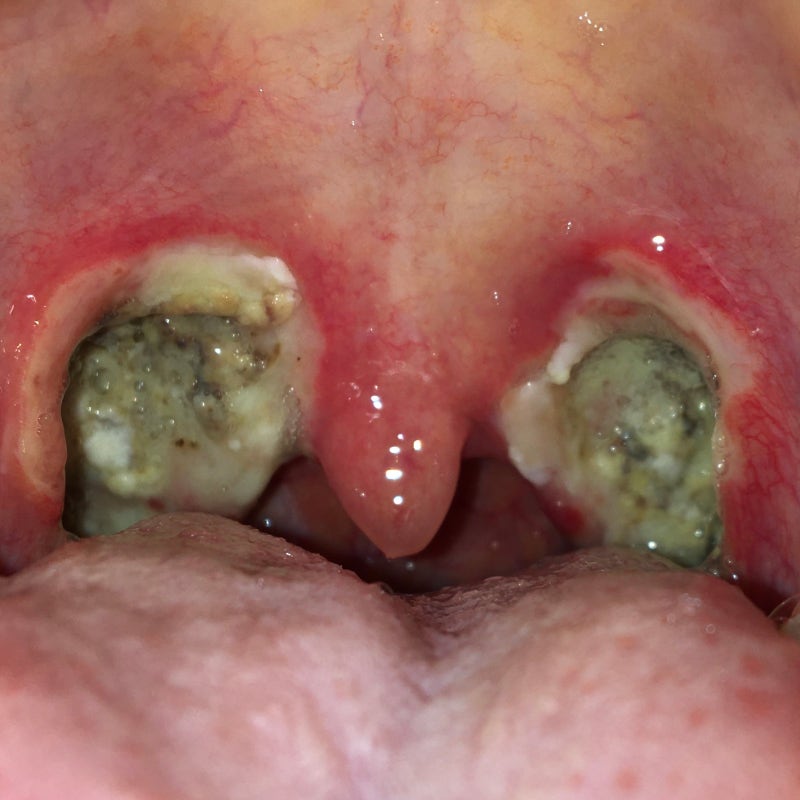

술 전, 후편도 사진 있어요. 싫어주의!! 20대 중반까지는 편도염에 엄청 걸렸고, 현재까지도 편도선이 커서… m.blog.naver.com

나흘째 되는 내 편도 어제와 마찬가지로 하루하루 지날수록 통증이 점점 커진다.

8일째 편도적이 약간 떨어졌다